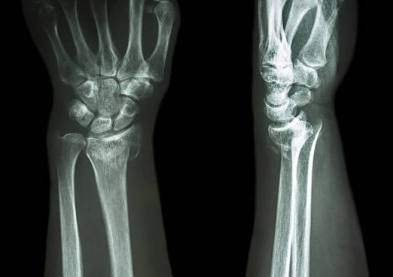

X-ray(방사선 촬영)으로 대부분 진단 가능

콜레스 골절(Colles' fracture): 골절 부위가 손등 쪽으로 밀려나 포크 모양 변형이 나타남

스미스 골절(Smith's fracture): 골절 부위가 손바닥 쪽으로 꺾임

바톤 골절(Barton's fracture): 관절면 일부가 골절되어 아탈구 또는 탈구 동반

원위 요골 골절은 손목을 짚고 넘어질 때 흔히 발생하는 골절로, 통증·붓기·변형 등이 주요 증상입니다. X-ray로 진단하며, 골절의 상태에 따라 석고 고정이나 수술적 치료를 시행합니다. 치료 후에는 손가락과 손목의 재활 운동이 매우 중요합니다.